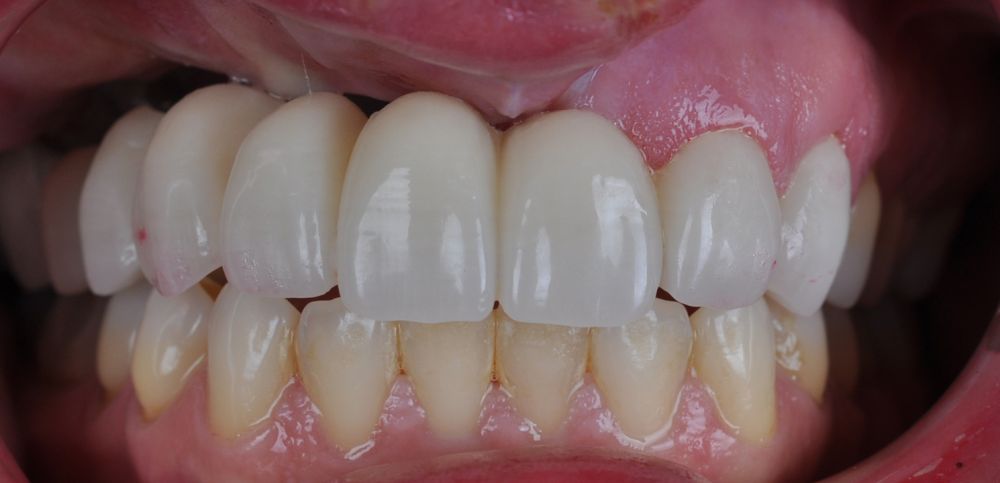

El día de la colocación de las estructuras, se arenó el interior de las coronas dentosoportadas con óxido de aluminio de 50 m y fueron cementadas con cemento de resina Multilink Ò. El puente implantosoportado se atornilló al torque indicado (20Nw) (Figuras 14, 15, 16 y 17).

En enero de 2021, el puente implantosoportado fue atornillado con un torque controlado (20 Nw), y las coronas dentosoportadas cementadas con éxito. La paciente refirió una notable mejoría en la función masticatoria, fonación y estética facial, manifestando un alto grado de satisfacción.

En el seguimiento a 4 años tras la colocación de la prótesis definitiva, no se observaron complicaciones mecánicas ni biológicas. La paciente continúa libre de enfermedad y con una correcta adaptación al tratamiento rehabilitador implantosoportado (Figura 18).